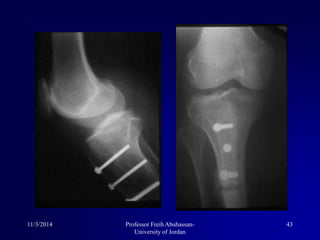

4-Treatment of associated pathologies

Patellar fracture secondary to luxation

4-Treatment of associatedpathologies Patellar fracture secondary to luxation 11/3/2014 25Professor Freih Abuhassan- University of Jordan